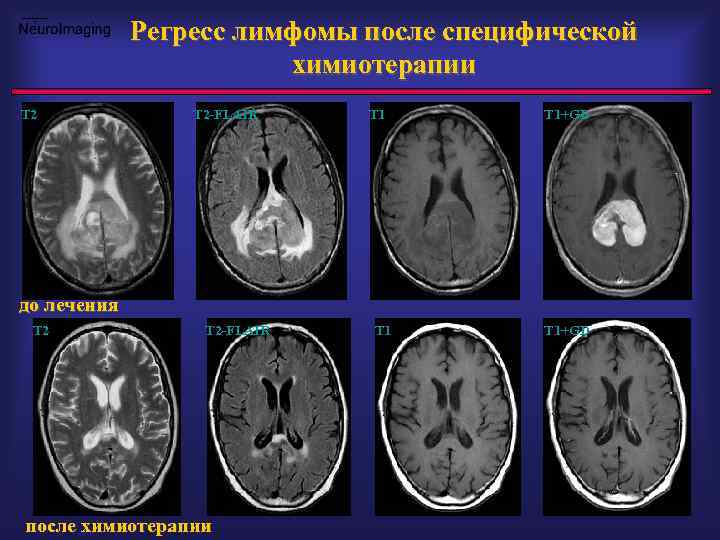

Регресс лимфомы после специфической химиотерапии T 2 -FLAIR T 1+GD до лечения T 2 -FLAIR после химиотерапии T 1+GD